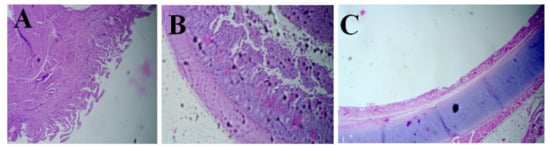

3.4. Histopathology Findings